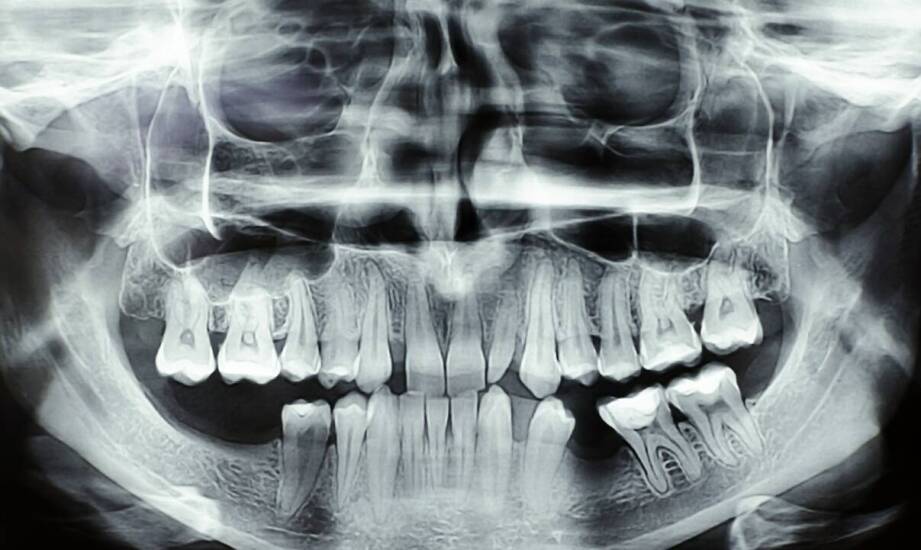

Tomografia komputerowa zębów (CBCT) to trójwymiarowe badanie, które w kilka–kilkanaście sekund pokazuje zęby, kości szczęk, zatoki i przebieg nerwów z precyzją niedostępną dla tradycyjnego RTG. Jest nieinwazyjna, szybka, a w wielu sytuacjach – jak planowanie implantów, skomplikowane leczenie kanałowe, chirurgia czy ortodoncja – bywa po prostu niezbędna. Poniżej wyjaśniamy, jak działa, kiedy lekarz ją zleca i czego oczekiwać w praktyce.

CBCT wykorzystuje stożkową wiązkę promieni X oraz detektor, który w jednym skanie zbiera setki projekcji. Komputer składa je w trójwymiarowy obraz (obrazowanie 3D) struktur jamy ustnej: zębów, kości, zatok przynosowych, stawów skroniowo‑żuchwowych i przebiegu kanału nerwu zębodołowego dolnego.

W odróżnieniu od klasycznego zdjęcia 2D, lekarz może obracać model, oglądać przekroje w dowolnej płaszczyźnie i dokładnie oceniać odległości, gęstość kości oraz relacje anatomiczne. To przekłada się na precyzję diagnostyczną i bezpieczniejsze planowanie zabiegów.

W porównaniu z RTG punktowym czy panoramicznym, CBCT pokazuje struktury w 3D z wyższą rozdzielczością przestrzenną. Dzięki temu widoczne stają się zmiany ukryte na zdjęciach dwuwymiarowych: pęknięcia korzeni, dodatkowe kanały, resorpcje, drobne torbiele oraz relacje z zatoką lub nerwem.